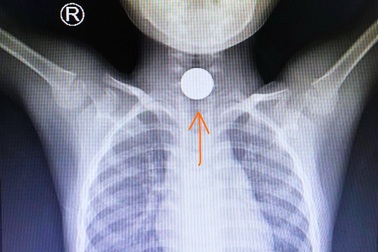

Nuốt đồng xu khi đi chúc Tết, bé trai 5 tuổi mắc nghẹn nguy kịchĐang đi mừng tuổi ngày mùng một Tết, bé trai ngậm đồng xu rồi nuốt nghẹn cổ họng, phải đi cấp cứu ngày đầu năm.